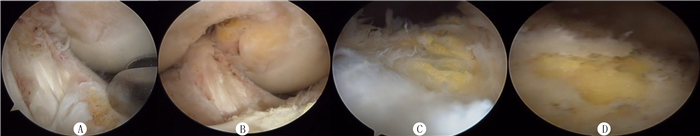

1.3 手术方法所有病人均在腰麻下手术,常规上气压止血带。病人取仰卧位,行关节镜下探查清理术,通过胫骨、股骨、髌骨三者体表投影关系,定位膝关节前内侧和前外侧入路,建立工作通道,插入镜头。顺序探查膝关节腔内髌上囊、内外侧间沟、髁间窝、内外侧间隙、股骨滑车和髌骨,打磨清理骨质增生的部分,切除增生滑膜,修整退变软骨及半月板(图 1A~D)。

| A:关节镜修整前股骨髁间窝软骨面退变、毛糙,滑囊褶襞增生;B:关节镜修整后股骨髁间窝软骨增生骨赘被剔除、软骨面打磨光滑;C:关节镜修整前股骨髁软骨面毛糙、退变;D:关节镜修整后股骨髁软骨面退变软骨脱屑被清除,关节软骨面尽可能修整光滑。 图 1 关节镜修整前后股骨髁软骨面变化情况 |